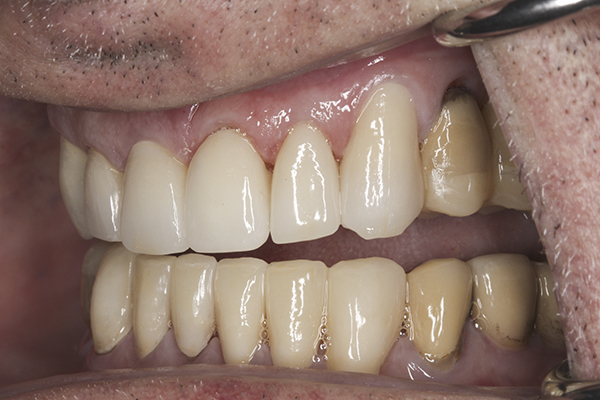

(35.) Postoperative right lateral, closed view.

Figure 35

(36.) Postoperative anterior, closed view. Note the position of the upper and lower canines to provide canine guidance.

Figure 36

(37.) Postoperative left lateral, closed view.

Figure 37